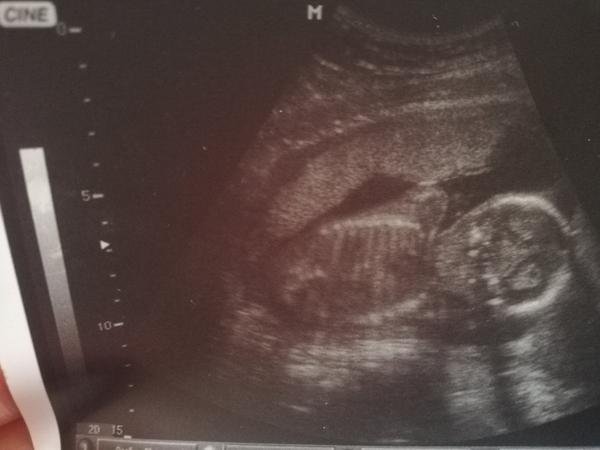

Přikládám dnešní foto z ultrazvuku